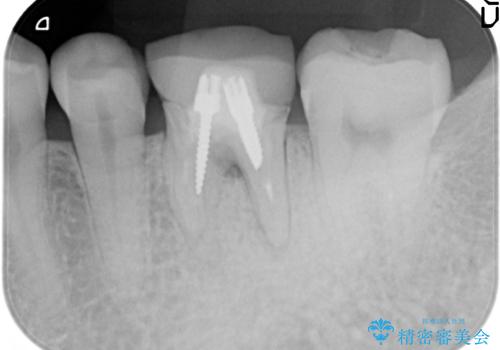

ストローマンについて

当院では主にストローマンという種類のインプラントを治療に用いています。

ストローマンは世界的にもNo1のシェアを誇り、骨との適合にも優れたインプラントです。